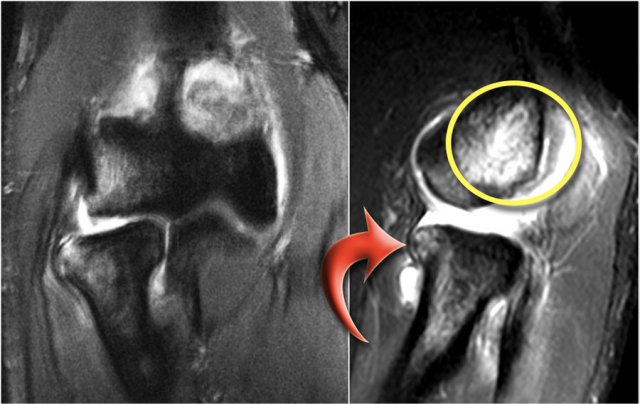

OC lesion of capitellum

Osteochondral lesion is the new name for osteochondritis dissecans or OCD.

The chronic valgus overload can cause an osteochondral lesion on the lateral side of the elbow.

It is the result of repetitive impaction and shear forces.

The MR-arthrogram confirms the osteochondral lesion.

There is gadolinium in between the humerus and the osteochondral lesion which indicates that it is unstable.

If you don't have gadolinium, look for joint fluid undercutting the fragment.

There is a loose body in the posterior recess of the radiocapittelar joint.

Notice also the fragmentation as seen on the axial image.

The osteochondral lesion of the capitellum is typically seen in throwers and gymnasts (11-15 yrs), who get a lot of wrist and elbow problems due to weight bearing.

Here another case in a 20 year old gymnast.

Again there is lucency on the radiograph.

The MR-arthrogram shows some bone marrow edema on the coronal view.

The sagittal T1W-image shows subchondral bone abnormality, but not much of a fragment.

There is some cartilage thinning, but not a defect.

This is obviously a stable fragment and there were no loose bodies.